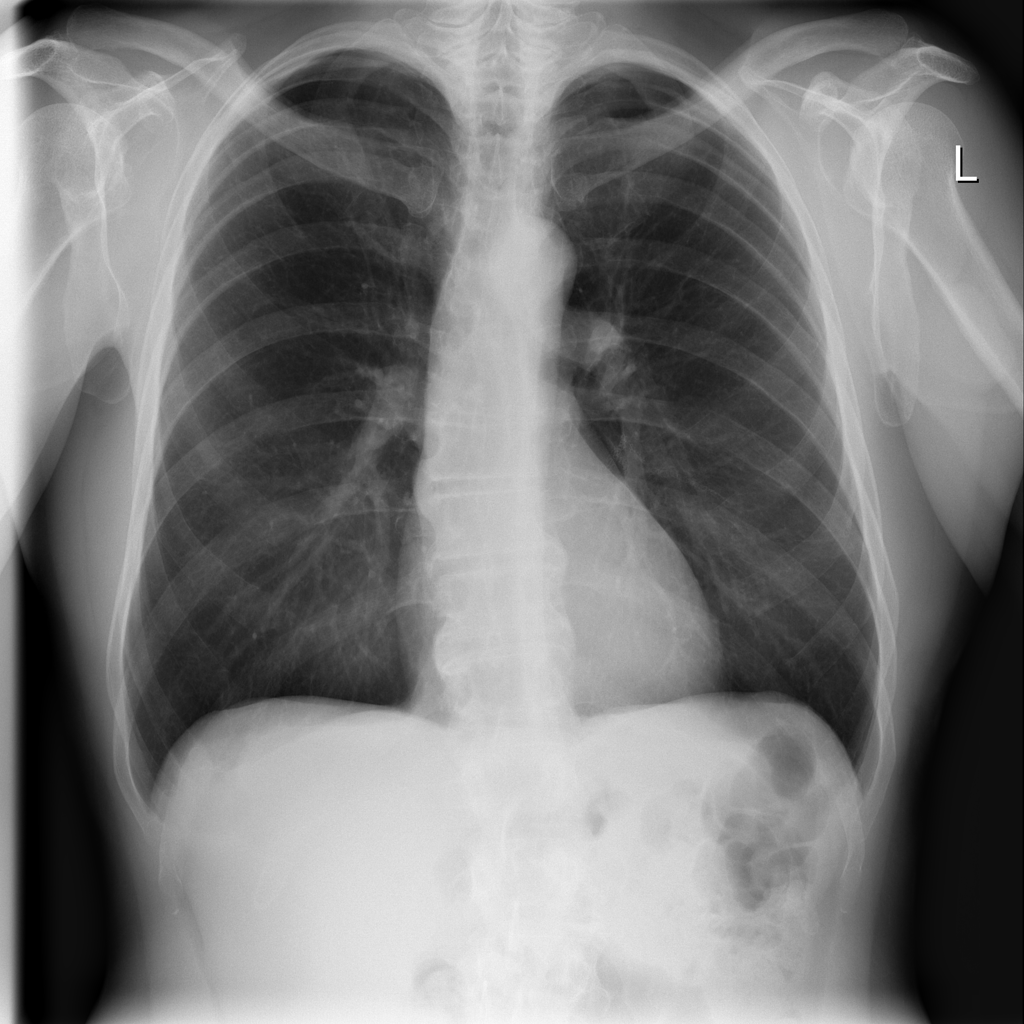

Showing up to 90 reference images for Emphysema.

PAT-894B · IMG-000Emphysema

PAT-894B · IMG-000

PA